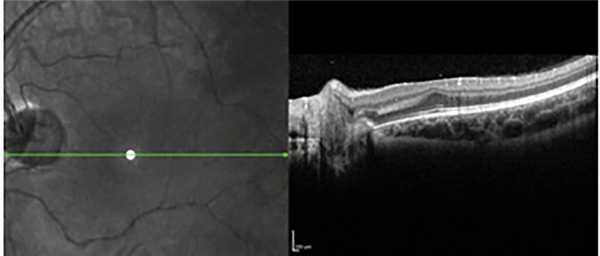

Результаты проведенной ОКТ показали, что у глубоко недоношенных детей с благоприятными исходами РН на 33 (61%) из 54 глаз отмечалось нарушение анатомического контура макулы. На 12 глазах с остаточными изменениями I—II степени сглаженность фовеолярного контура в совокупности с сохранностью эмбрионального строения макулы (слоев нейроэпителия в фовеа) свидетельствовала о нарушении дифференцировки макулы вследствие недоношенности, и лишь на трех глазах она сопровождалась снижением остроты зрения ниже 0,3. На 10 глазах со II степенью РН сглаженность фовеолярного контура сопровождалась наличием структурных изменений (кистовидный отек и тракционная деформация нейроэпителия), невидимых при офтальмоскопии, что и объясняло некорригируемое снижение остроты зрения. При III степени РН сформированный фовеолярный контур и сохранность слоев нейроэпителия в макуле выявлены только на двух глазах. В остальных случаях фовеолярный контур был сглажен или отсутствовал вследствие тракционной деформации макулы после перенесенной РН и коррелировал со сниженной остротой зрения (рис. 7).

Рис. 7. Сглаженный фовеолярный контур и тракционная деформация сетчатки на глазу с рубцовой РН III степени.